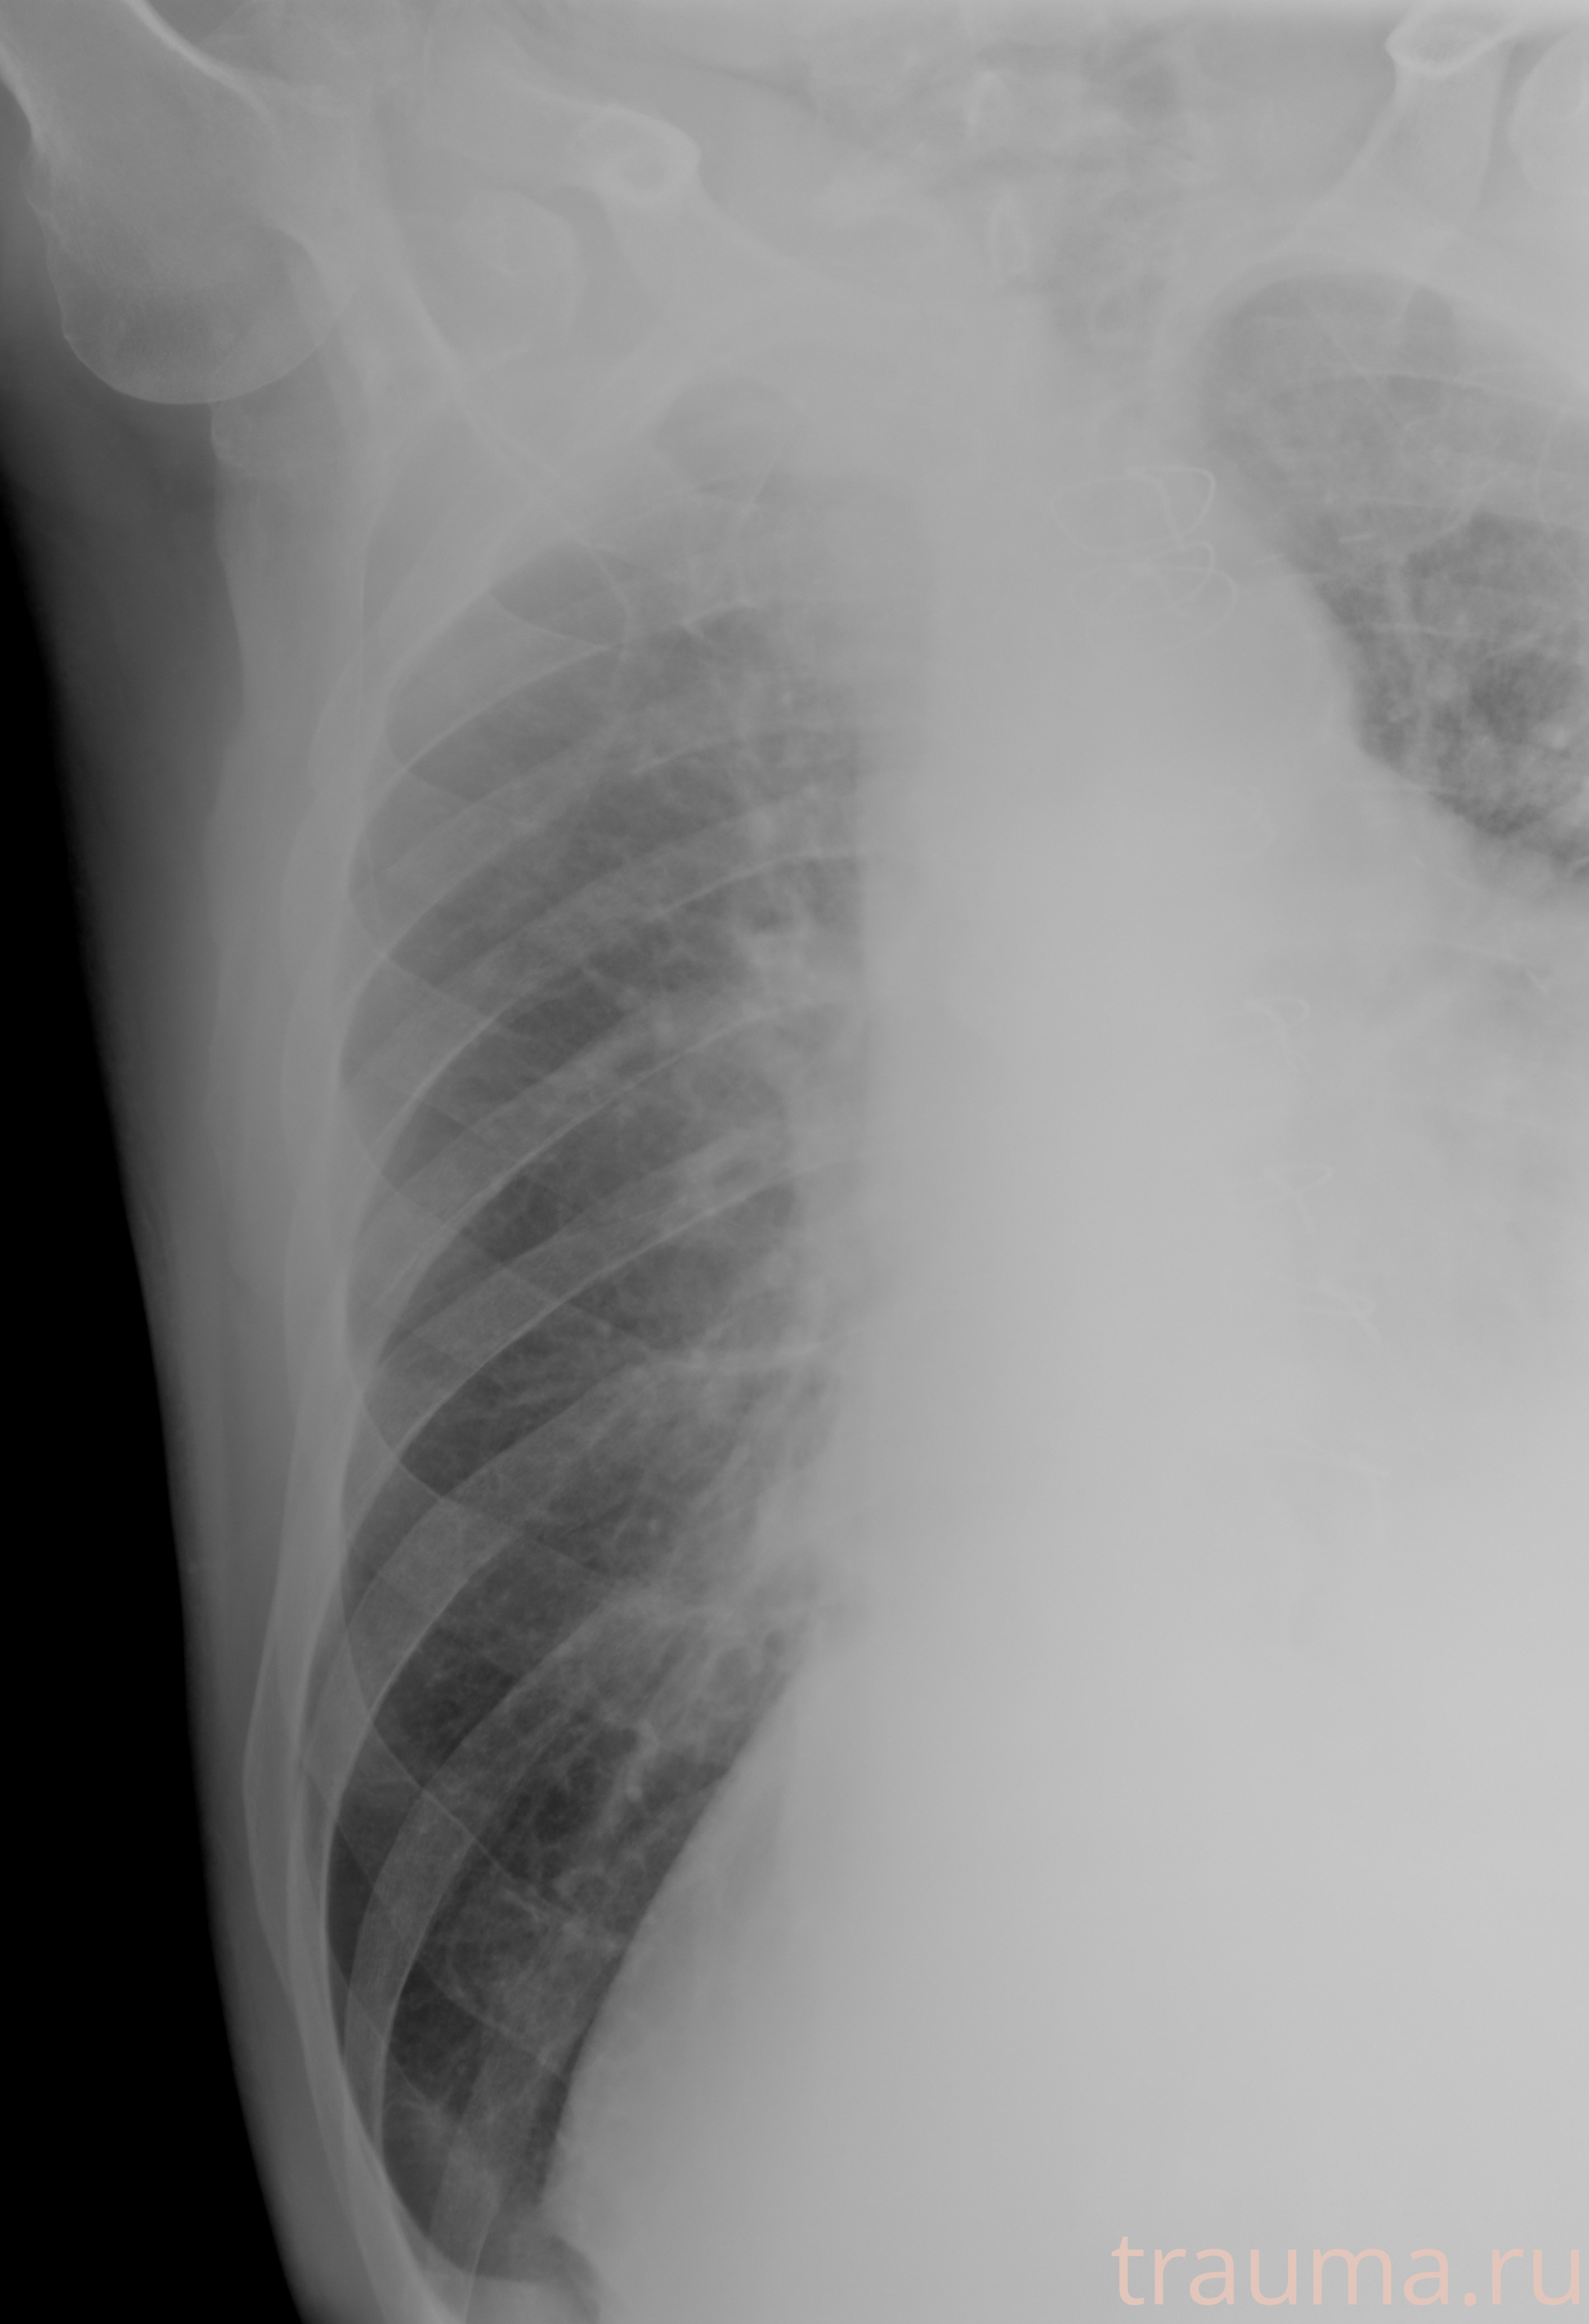

Рентген на дому: по вашему адресу приезжает врач-рентгенолог, травматолог-ортопед с мобильным рентгеновским аппаратом, проводит диагностику травмы или заболевания, делает необходимые рентгенограммы, дает рекомендации по дальнейшему лечению. Получить качественные снимки в домашних условиях возможно благодаря уникальной методике, разработанной МосРентген Центром для института  Склифосовского

при переломе шейки бедра и пневмонии от компании МосРентген Центр - партнера Института имени Склифосовского